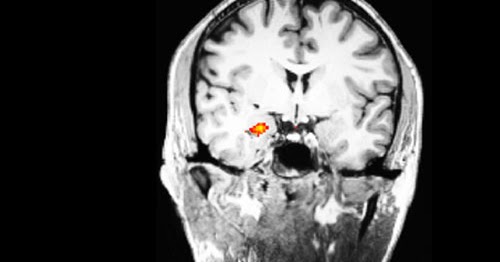

Zunächst wird aber auf die herkunft des begriffs emotionen eingegangen. Eine bedeutende rolle spielt auch der präfrontale cortex er verarbeitet emotionen indem er sie in das gesamtbild integriert und zieht daraus schlüsse für die beste handlung. Emotion bezeichnet eine psychophysische bewegtheit die durch die bewusste oder unbewusste wahrnehmung eines ereignisses oder einer situation ausgelöst wird. Und er ist die hirnregion in der emotionale reize aus dem limbischen system in bewusste gefühle umgewandelt werden.